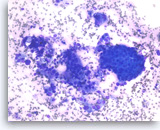

Plasma cell neoplasm,

Pancreas FNA, Direct Smear.

The aspirates show dispersed single cells with a prominent plasmacytoid appearance. The tumor cells vary slightly in size. Rare mitoses are seen.

20X

Plasma cell neoplasm,

Pancreas FNA, Direct Smear.

The aspirates show dispersed single cells with a prominent plasmacytoid appearance. The tumor cells vary slightly in size. Rare mitoses are seen.

20X